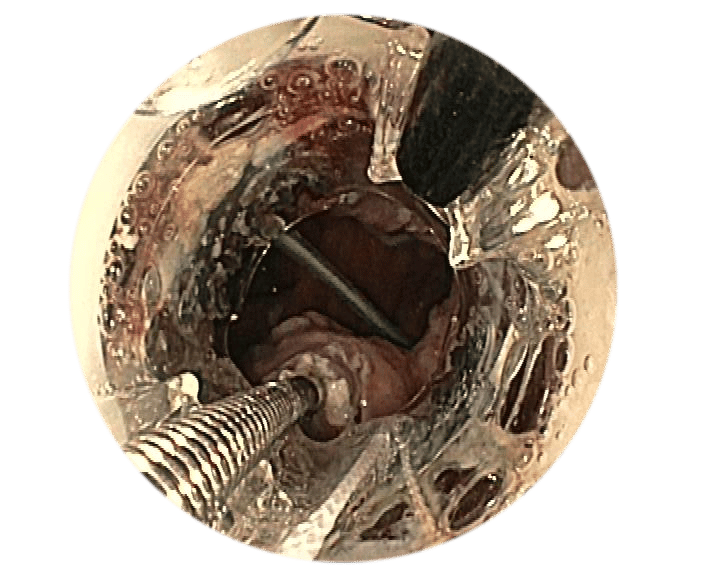

Anvisieren der Applikationsstelle.

Einführen des Führungsdrahts in den äußeren BARS® Arbeitskanal und Vorlegen in der Anastomose.

Einführen der Anker in den Endoskop-Arbeitskanal und den inneren BARS® Arbeitskanal.

Überkreuztes Platzieren der Anker im vorbereiteten Zielgewebe.

Platzieren des Kalibrierballons in der Anastomose. Schrittweises Einziehen des Gewebes in die BARS® Applikationskappe, mit abwechselnden Zugbewegungen.

Sicherstellen, dass das Gewebe symmetrisch in der Kappe positioniert ist. Platzieren des BARS® Clips durch Drehen des Handrads.

Zurückziehen der Instrumente und Inspektion der Clip-Applikationsstelle.

1Quelle: Dr. med. M. Kandler, Städtisches Klinikum Dresden, Deutschland